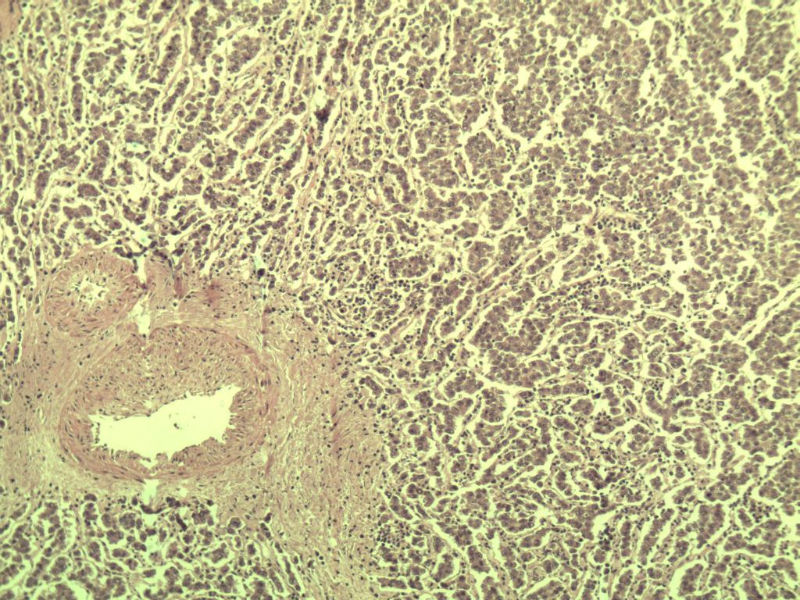

男 27岁 腹腔隐睾 5*3*2 cm, 切面灰红灰黄、实性、质中,请各位老师看看,是精原细胞瘤吗?感觉不像.